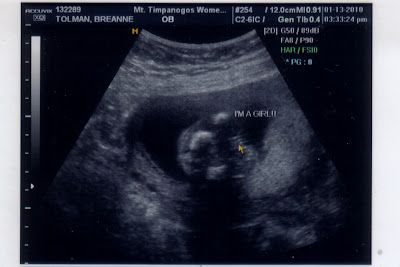

That's right!  We're having a GIRL!!!!!

I'm just completely floored, but excited.  She really is a very huge blessing because I don't have to buy ANY clothes for her (Mara's bday is in April, and she is due in June).  Hopefully there's enough of a span between the girls that Mara won't feel threatened when she's old enough to want to play with Mara's princess toys!

So there you have it!  Now it's just really deciding on a name. We have one in mind, but I'm not sure if it's right.